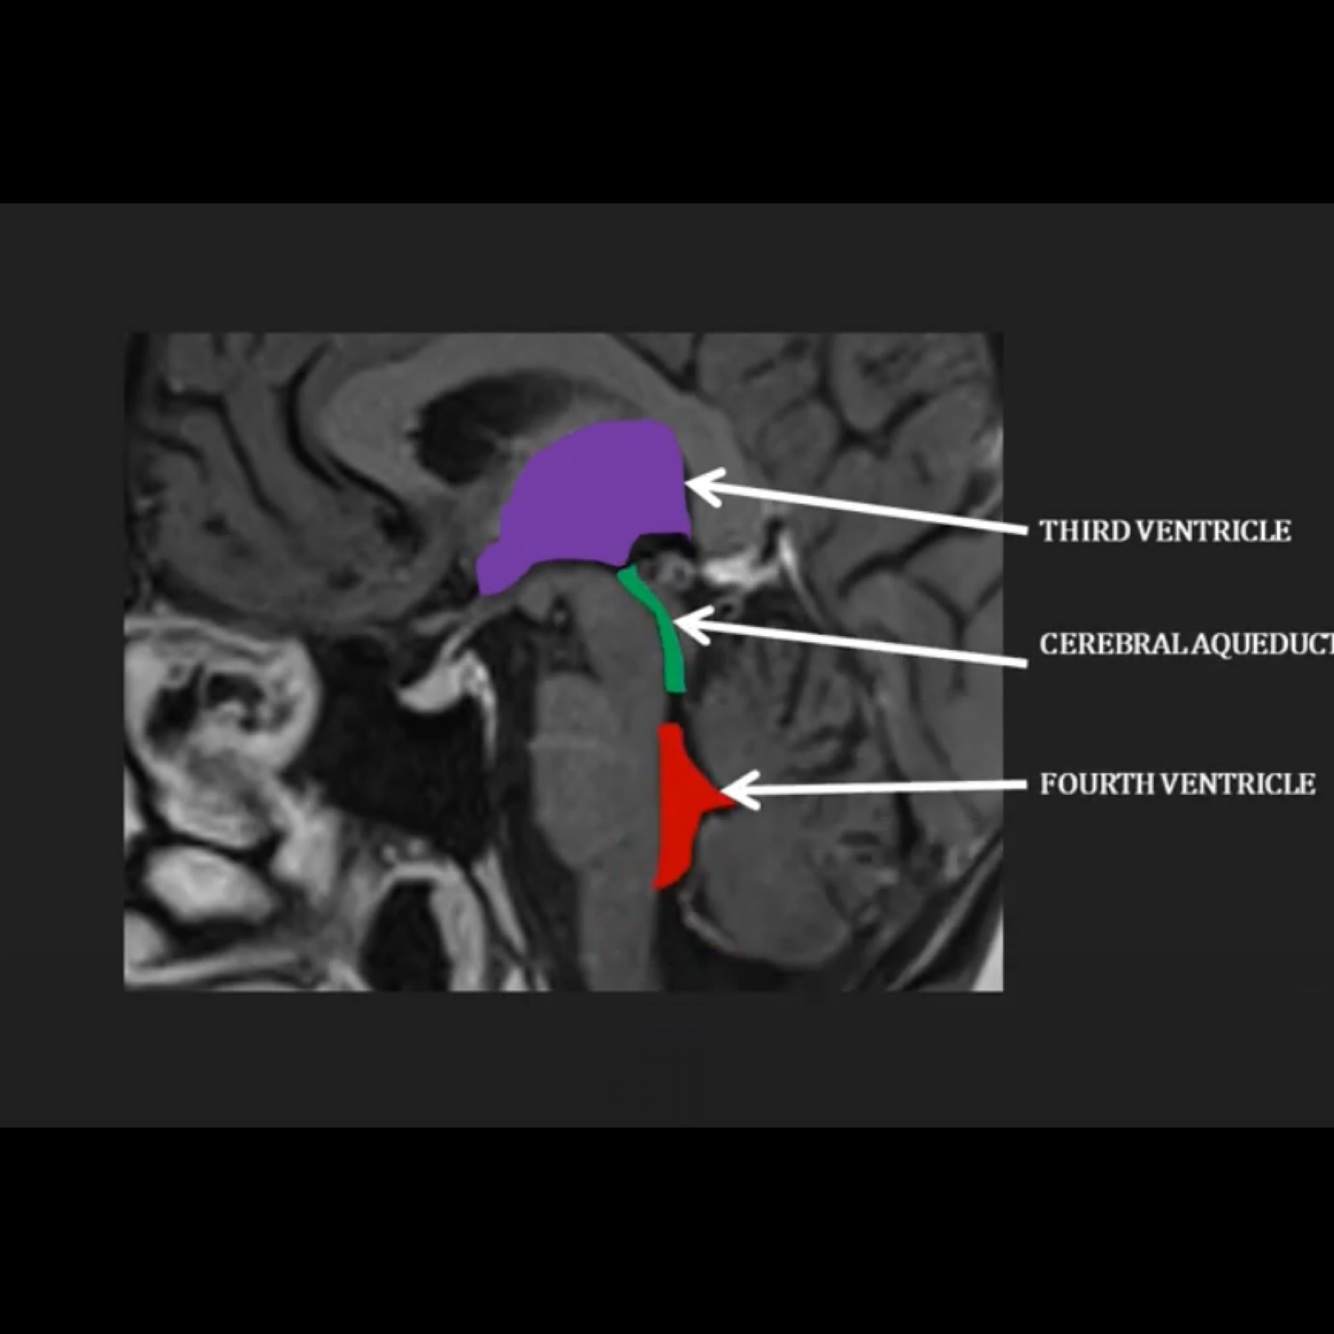

Where does the CSF flow through the brain as visible on this diagram?

Through the third ventricle into the cerebral aqueduct, into the fourth ventricle